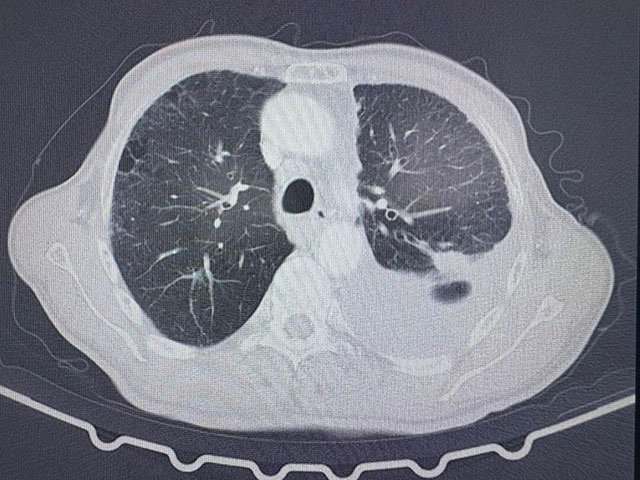

入院時,張爺爺?shù)牟∏橐咽治<?,胸心外科副主任劉浩副教授檢查發(fā)現(xiàn):左肺存在惡性結(jié)節(jié),左側(cè)胸腔中量積液,肺部感染嚴(yán)重。

術(shù)前胸部CT